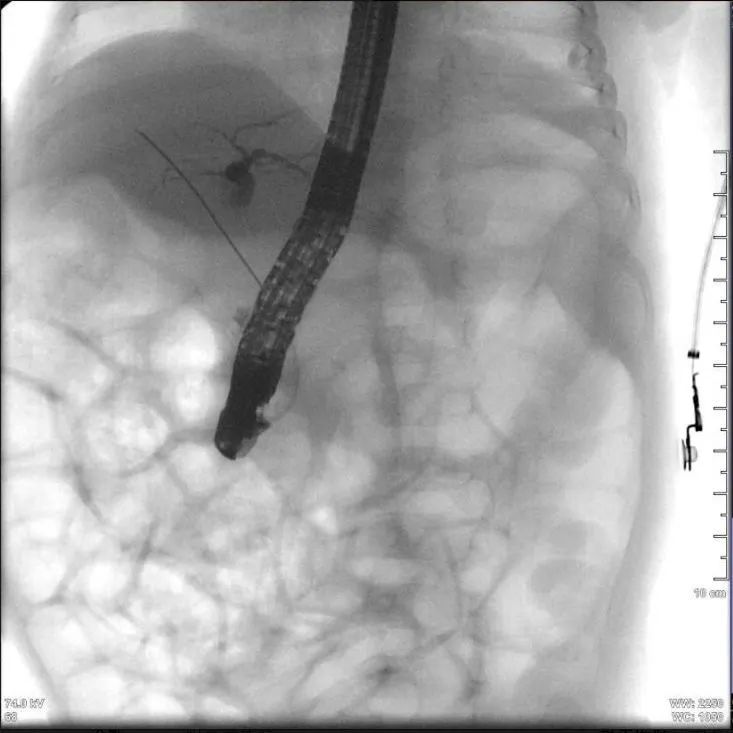

ERCP插管成功

手术当日,在医院通州院区内镜中心,麻醉手术中心李娜主治医师为患儿进行了全麻气管插管,内镜中心护师杜建枕巧用注射器为患儿特制了一个内镜咬口,防止术中对患儿口腔的损伤,并用铅衣与护颈为患儿构建起双重防护屏障。消化中心刘春涛主任医师、赵桂平主治医师展开操作,当内镜缓缓进入患儿消化道,所有人的心都悬到了嗓子眼。最终,凭借顶尖技术,医疗团队在毫米级操作空间里顺利完成了超高难度的ERCP操作,成功置入了救命的胆管支架,瞬间打通淤堵的生命通道。